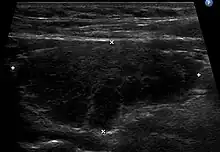

Ultrasound

An ultrasound may be useful in detecting Hashimoto thyroiditis, especially in those with seronegative thyroiditis,[15] or when patients have normal laboratory values but symptoms of autoimmune thyroiditis.[52] Key features detected in the ultrasound of a person with Hashimoto's thyroiditis include "echogenicity, heterogeneity, hypervascularity, and presence of small cysts."[15] Images obtained with ultrasound can evaluate the size of the thyroid, reveal the presence of nodules, or provide clues to the diagnosis of other thyroid conditions.[52]